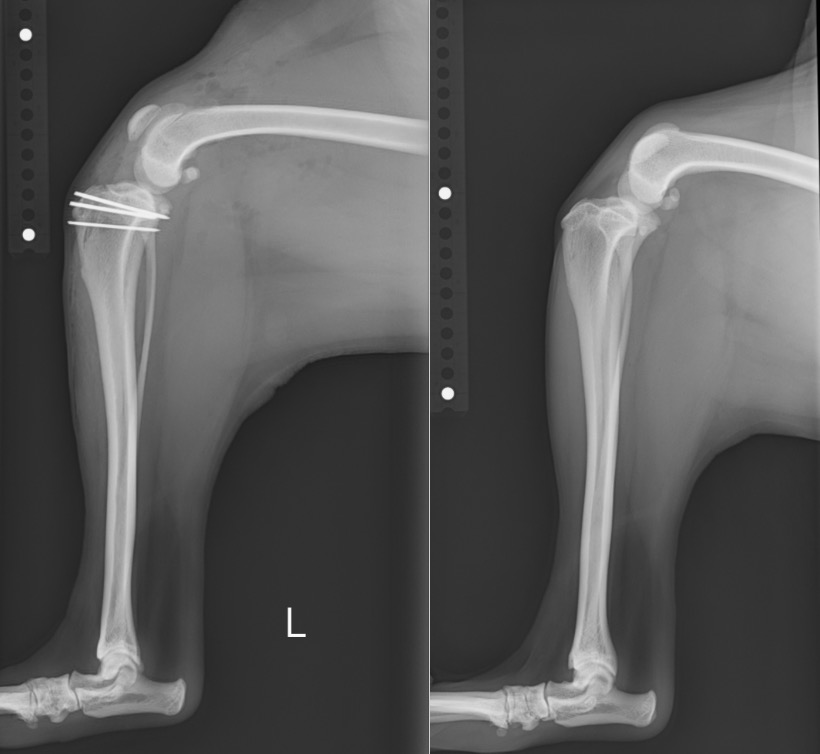

術前・術後のX線を見比べると、膝蓋骨が真ん中に整復されていることが分かります。

白く見えるのはステンレス製のピンであり、脛骨粗面転移という手技を行ったために使っています。

左後肢 【左:術後 / 右:術前】